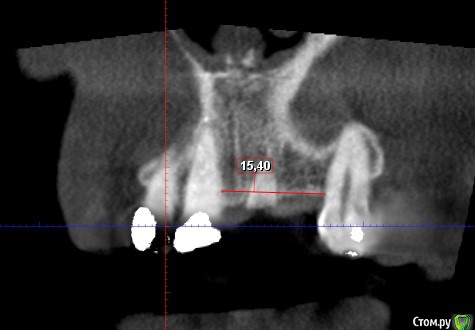

Дмитрий М Опубликовано 29 декабря, 2018 Поделиться Опубликовано 29 декабря, 2018 (изменено) Техник сделает восковой прогноз. И С него сделает шаблон. Больше для подстраховкипокажите пожалуйста фото шаблона и на КТ ширина гребня 9,11мм? срезы корректно выставлены? Изменено 29 декабря, 2018 пользователем Дмитрий М Ссылка на комментарий

bogdan_r Опубликовано 29 декабря, 2018 Автор Поделиться Опубликовано 29 декабря, 2018 (изменено) покажите пожалуйста фото шаблона и на КТ ширина гребня 9,11мм? срезы корректно выставлены?Шаблон будет после нг. Позиция импланта будет немного другая. Ширина в самом узком месте 9.11мм Изменено 29 декабря, 2018 пользователем bogdan_r Ссылка на комментарий